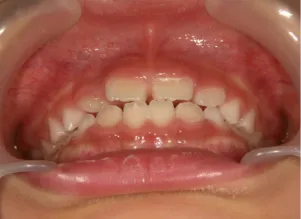

治療中➁小2(7y3m):成長期受け口用ファンクショナルアプライアンススタート

治療中③小2(7y8m):JUMP 受け口が改善

| 行ったご提案・診断内容 | 成長期に行う治療と咬合治療をご提案 受け口用ファンクショナルアプライアンス(写真②③)からスタートし、小2以降で上下顎の拡大・歯列弓の形態修正・前歯の並べ直し(写真④)を行いその後、モノブロック(筋機能的咬合誘導)装置(写真⑤)へ移行し、受け口の再発予防と永久歯を適切な咬み合わせに誘導し、必要によりマルチブラケット法へ移行する治療方法を提案しました。 成長期治療(成長時期にお口の環境を整える治療) 2年生以降から 咬合治療 |

| 治療期間 | 12か月:受け口用ファンクショナルアプライアンス(写真②③) 12カ月:成長期治療の動的治療期間(写真④) 現在、成長の経過観察と咬合誘導中です(写真⑤~⑨) |